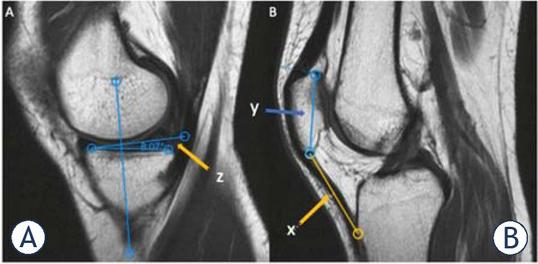

Figure 1